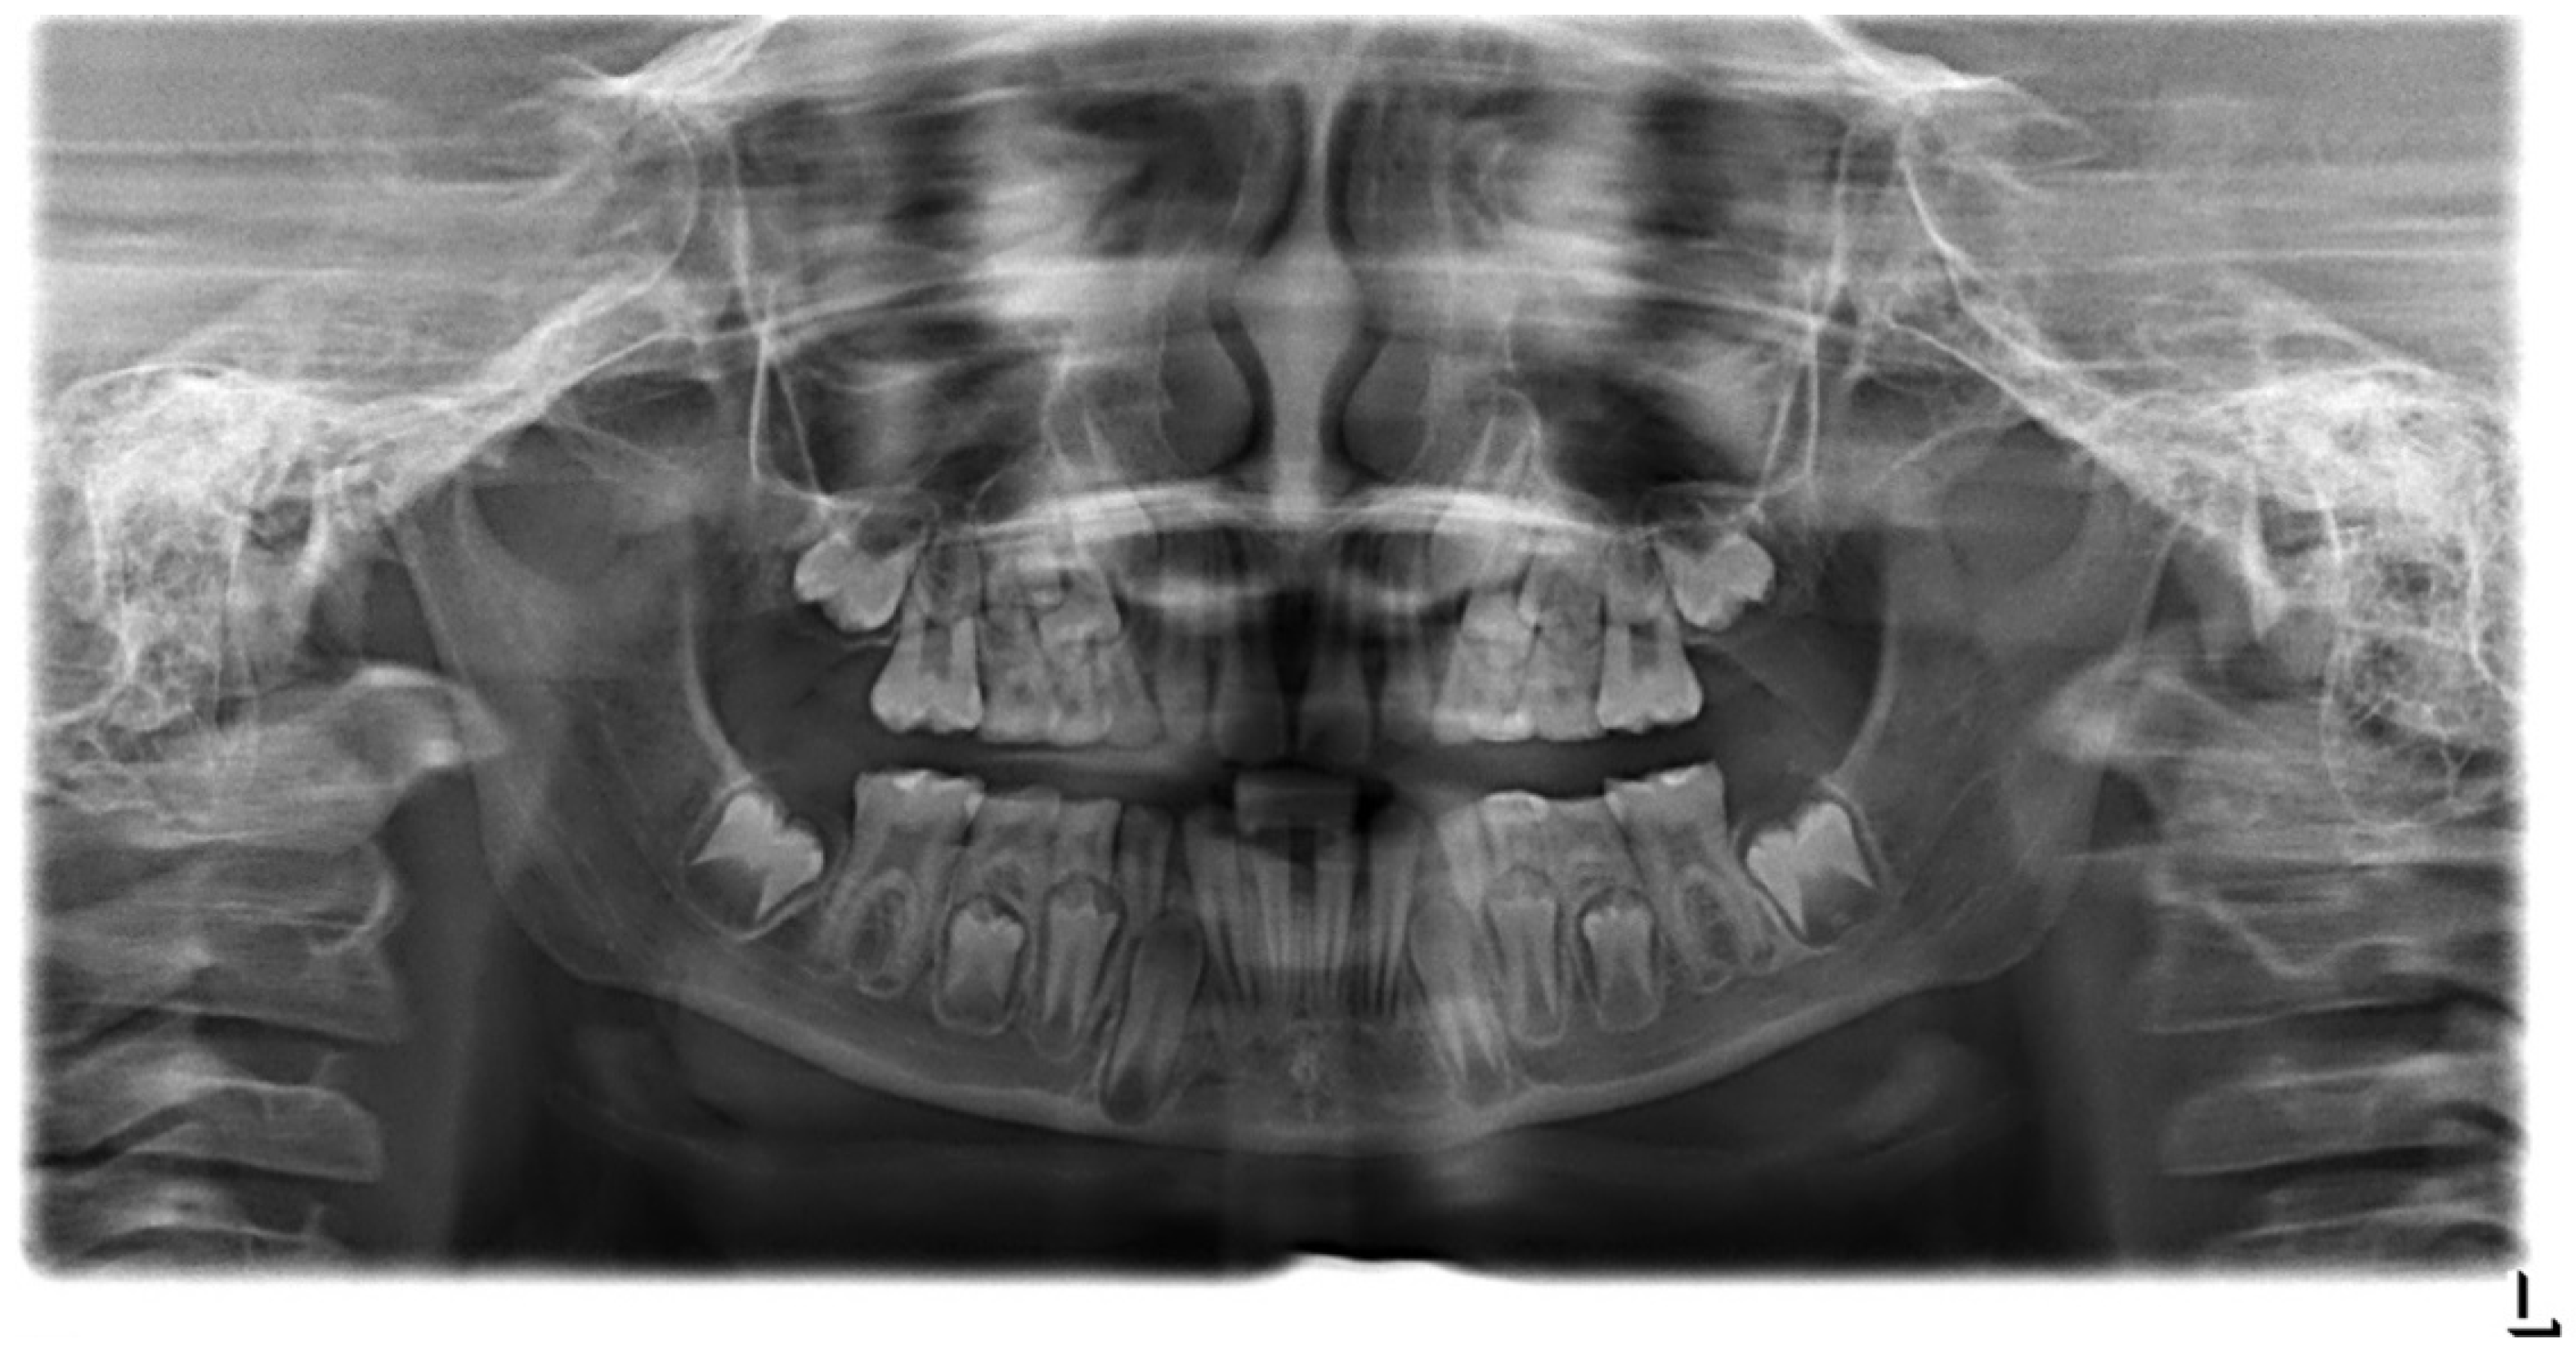

2.2. Case Report: Permanent Dentition